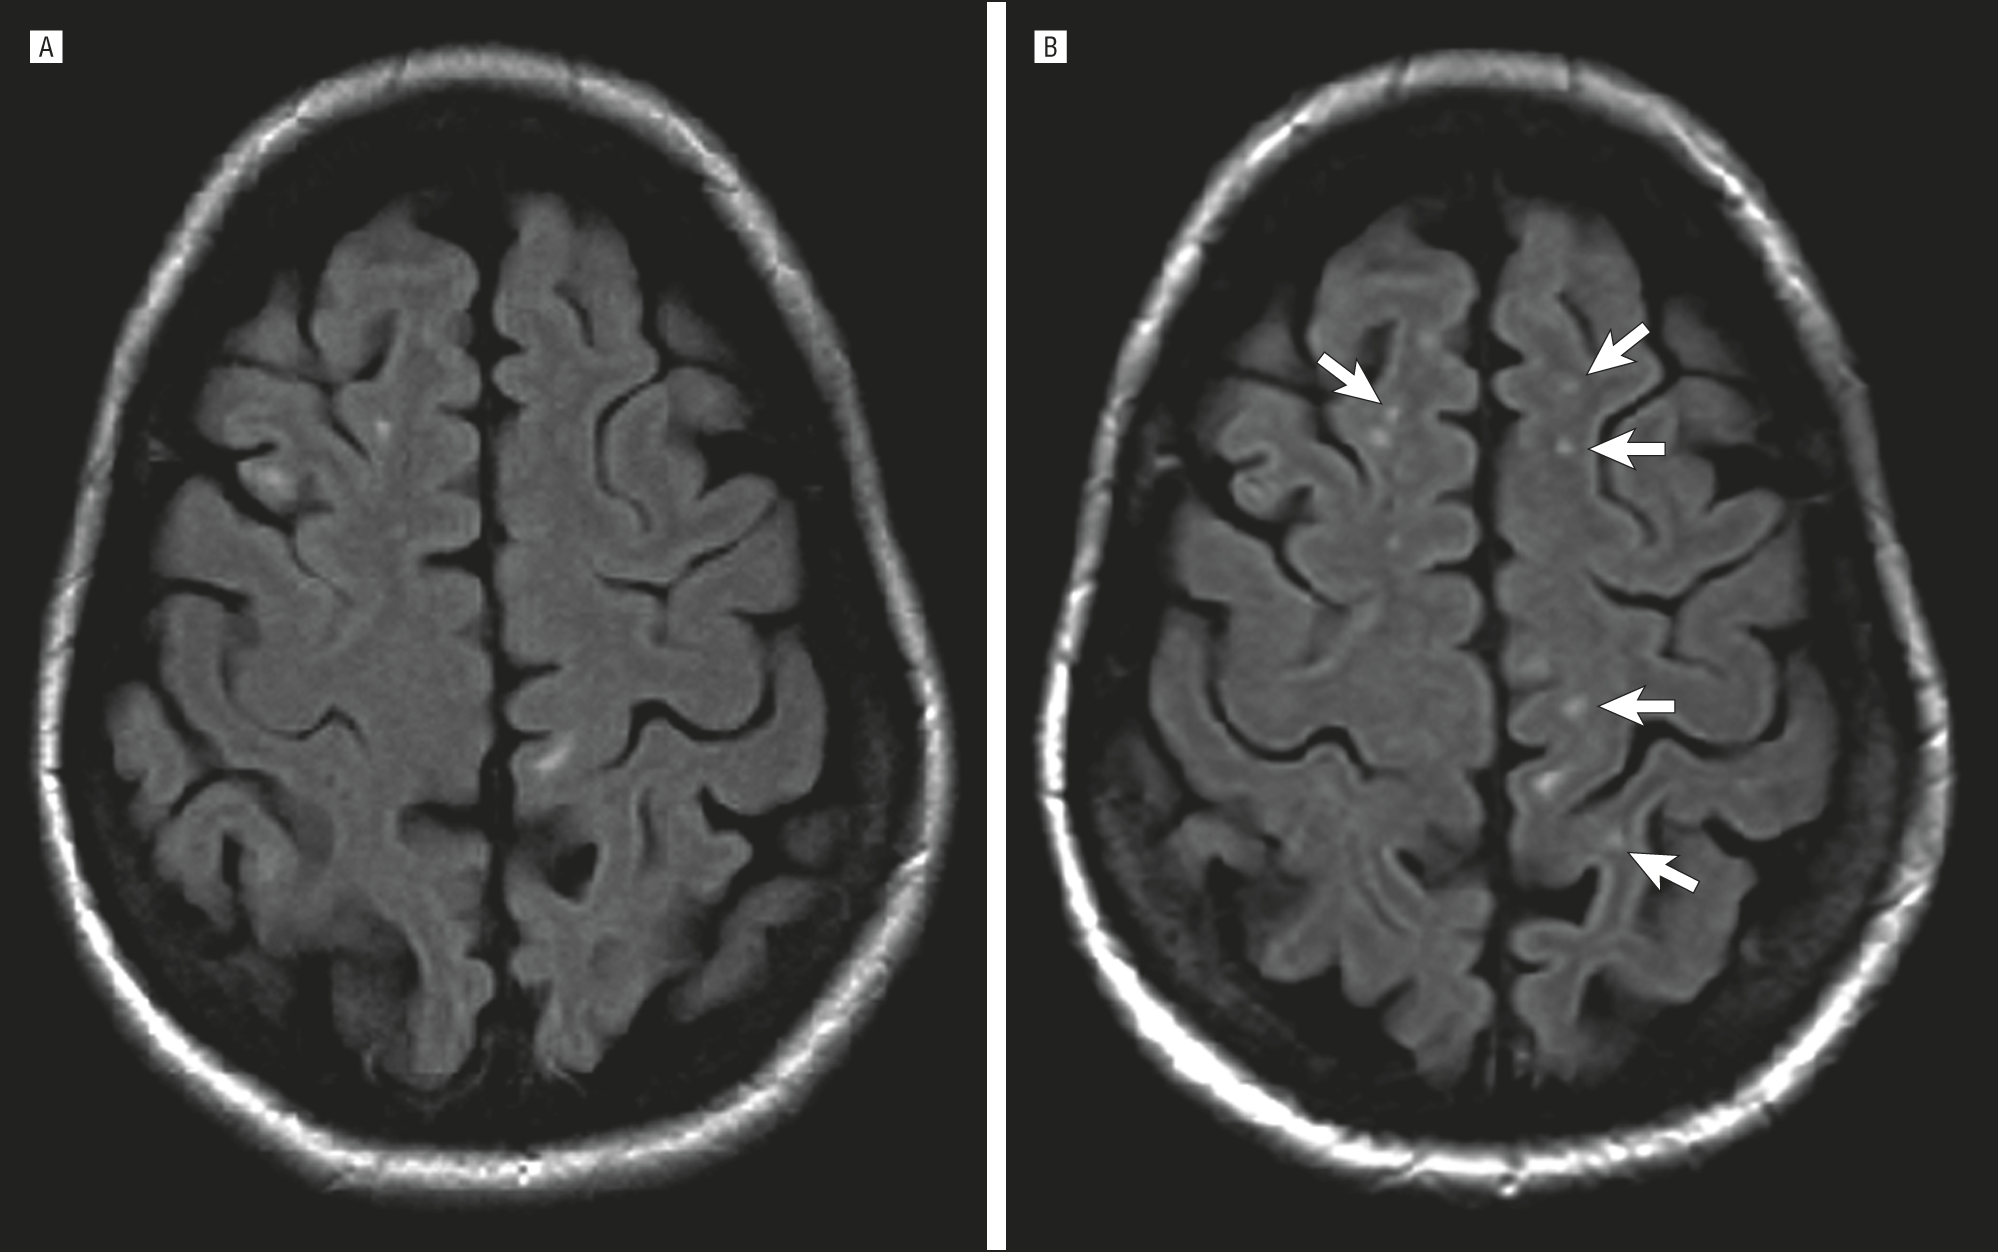

Демиелинизирующие заболевания мозга: МРТ изображения